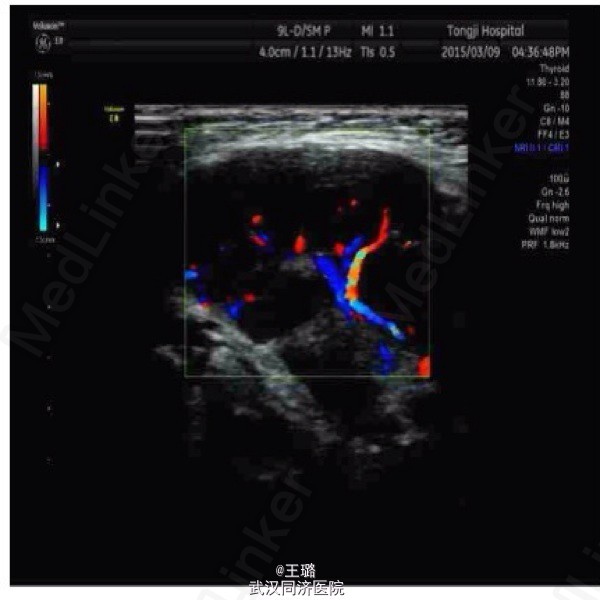

IgG相关性眼眶肿块

患者,男,11岁,一个月前发现双侧眼睑处肿块入院。入院体检:眼睑肿物伴溃疡,腮腺淋巴结、颌下淋巴结肿大。实验室检查示:抗Sm抗体阳性,IgG抗体阳性,影像学示:眼睑部高密度影。考虑为IgG相关性炎性假瘤,手术切除肿块并激素治疗,患者目前情况良好。